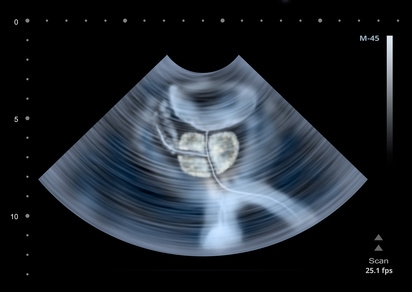

ProstatakrebsDiagnose von Prostatakrebs mit künstlicher Intelligenz von menscore 31. Juli 2018 Prostatakrebs ist die häufigste Krebserkrankung bei Männern in Deutschland. Jährlich werden rund 63.400 Neuerkrankungen diagnostiziert. Neben einer Tast- und einer Blutuntersuchung spielen bei der Diagnose Ultraschallverfahren eine entscheidende Rolle, jetzt auch kombiniert mit künstlicher Intelligenz. Weiterlesen

ProstatakrebsPSA-Test zur Früherkennung von Prostatakrebs von menscore 9. April 2017 Unter keiner anderen Krebsart leiden Männer so häufig, wie unter Prostatakrebs. Eine Früherkennung ist daher unverzichtbar, denn im Frühstadium bestehen die besten Heilungschancen. Zur gesetzlich garantierten Krebsvorsorge zählt hierzulande lediglich das Abtasten der Prostata. Tiefer liegende Tumore können dabei durchaus übersehen werden. Eine bessere Gewissheit kann hier ein PSA-Test schaffen. Weiterlesen

ProstatakrebsProstatakrebs – das sollte man wissen von menscore 15. November 2016 Prostatakrebs kann sehr unterschiedlich verlaufen. Der Krebs breitet sich meist sehr langsam aus, ohne signifikante körperliche Beschwerden zu machen. Es gibt jedoch auch Krebsarten, die sehr aggressiv sind und sich ohne entsprechende Behandlung schnell ausbreiten. Was man über den häufigsten Krebs des Mannes wissen sollte. Weiterlesen